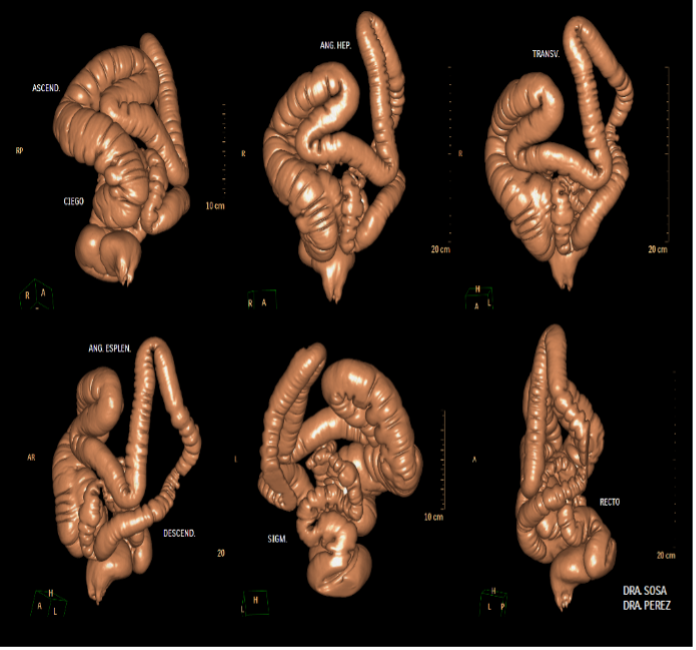

| POSPROCESAMIENTO DE IMÁGENES TOMOGRÁFICAS DE COLON PARA DIAGNOSTICAR CASOS DESAFIANTES. Autor: Dr. SERGIO MARTINEZ-MILLAN - Volumen 79 (4) GEN 2025 | |